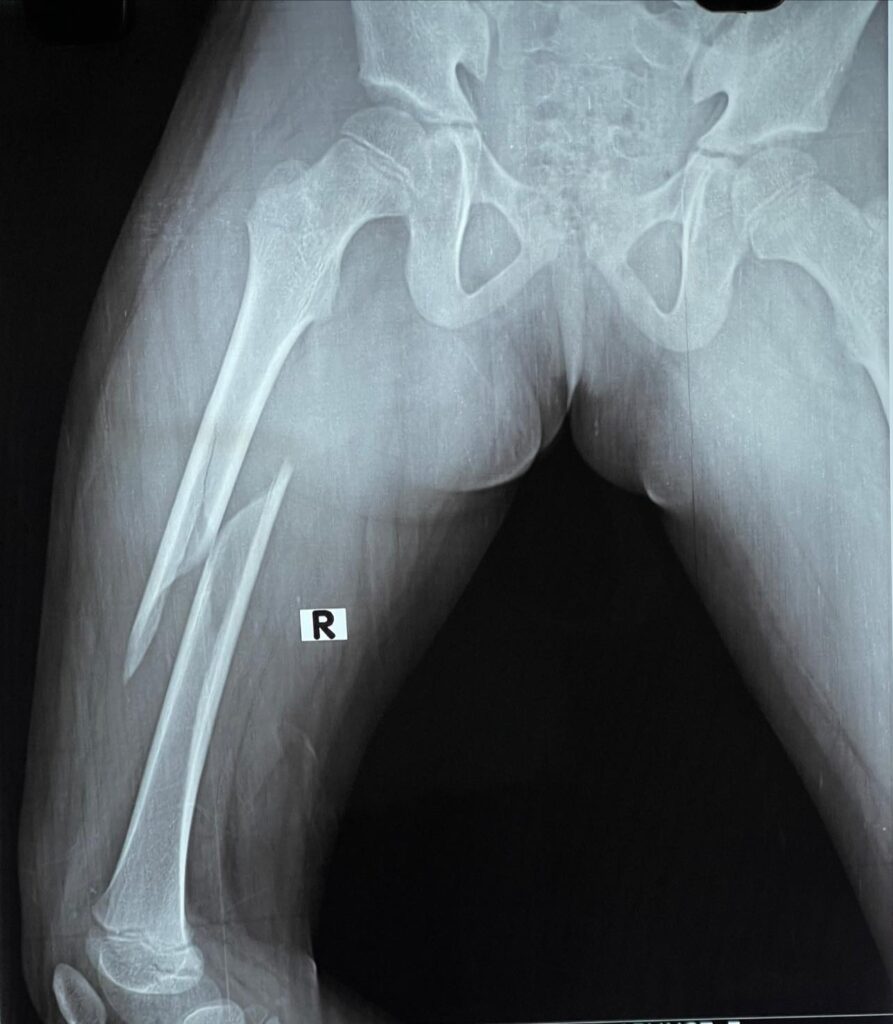

Neck of Femur Fractures

Most neck of femur fractures are treated with partial or total jointreplacement surgeries. however doing so limits active lifestyle in younger individuals. Especially in the Indian system of living. that is why it’s important to take such fractures as surgical emergencies in young people like this 43 year old woman and treat them with screw […]